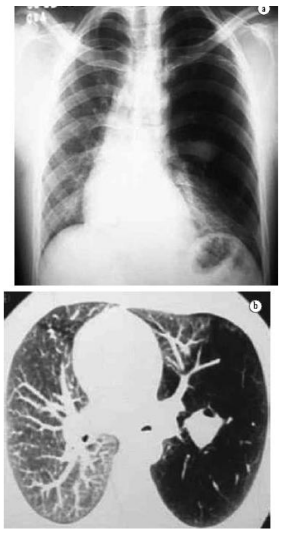

Analise as imagens para responder à questão

Considere a imagem para responder à questão.